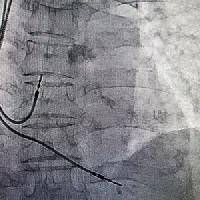

Выезд травматолога-ортопеда, рентгенолога Александра Валерьевича Дидковского.

Изучение проблемы низкого качества рентгенограмм на Вашем оборудовании.